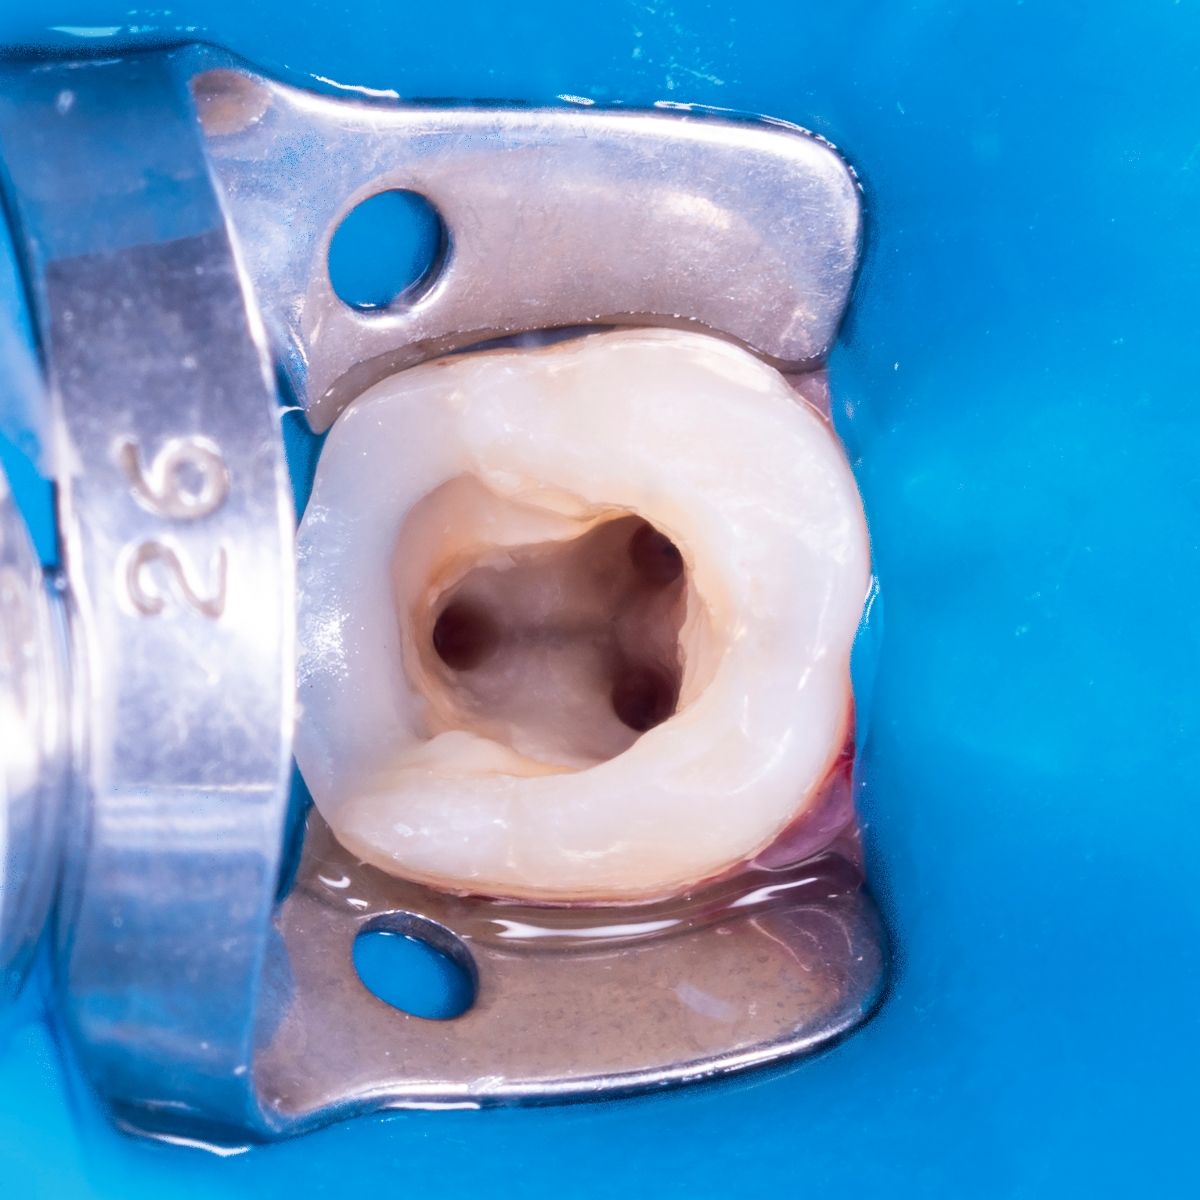

Root canal treatment

careful treatment of canals

Accurate determination of the geometry of the channels and their high-quality processing